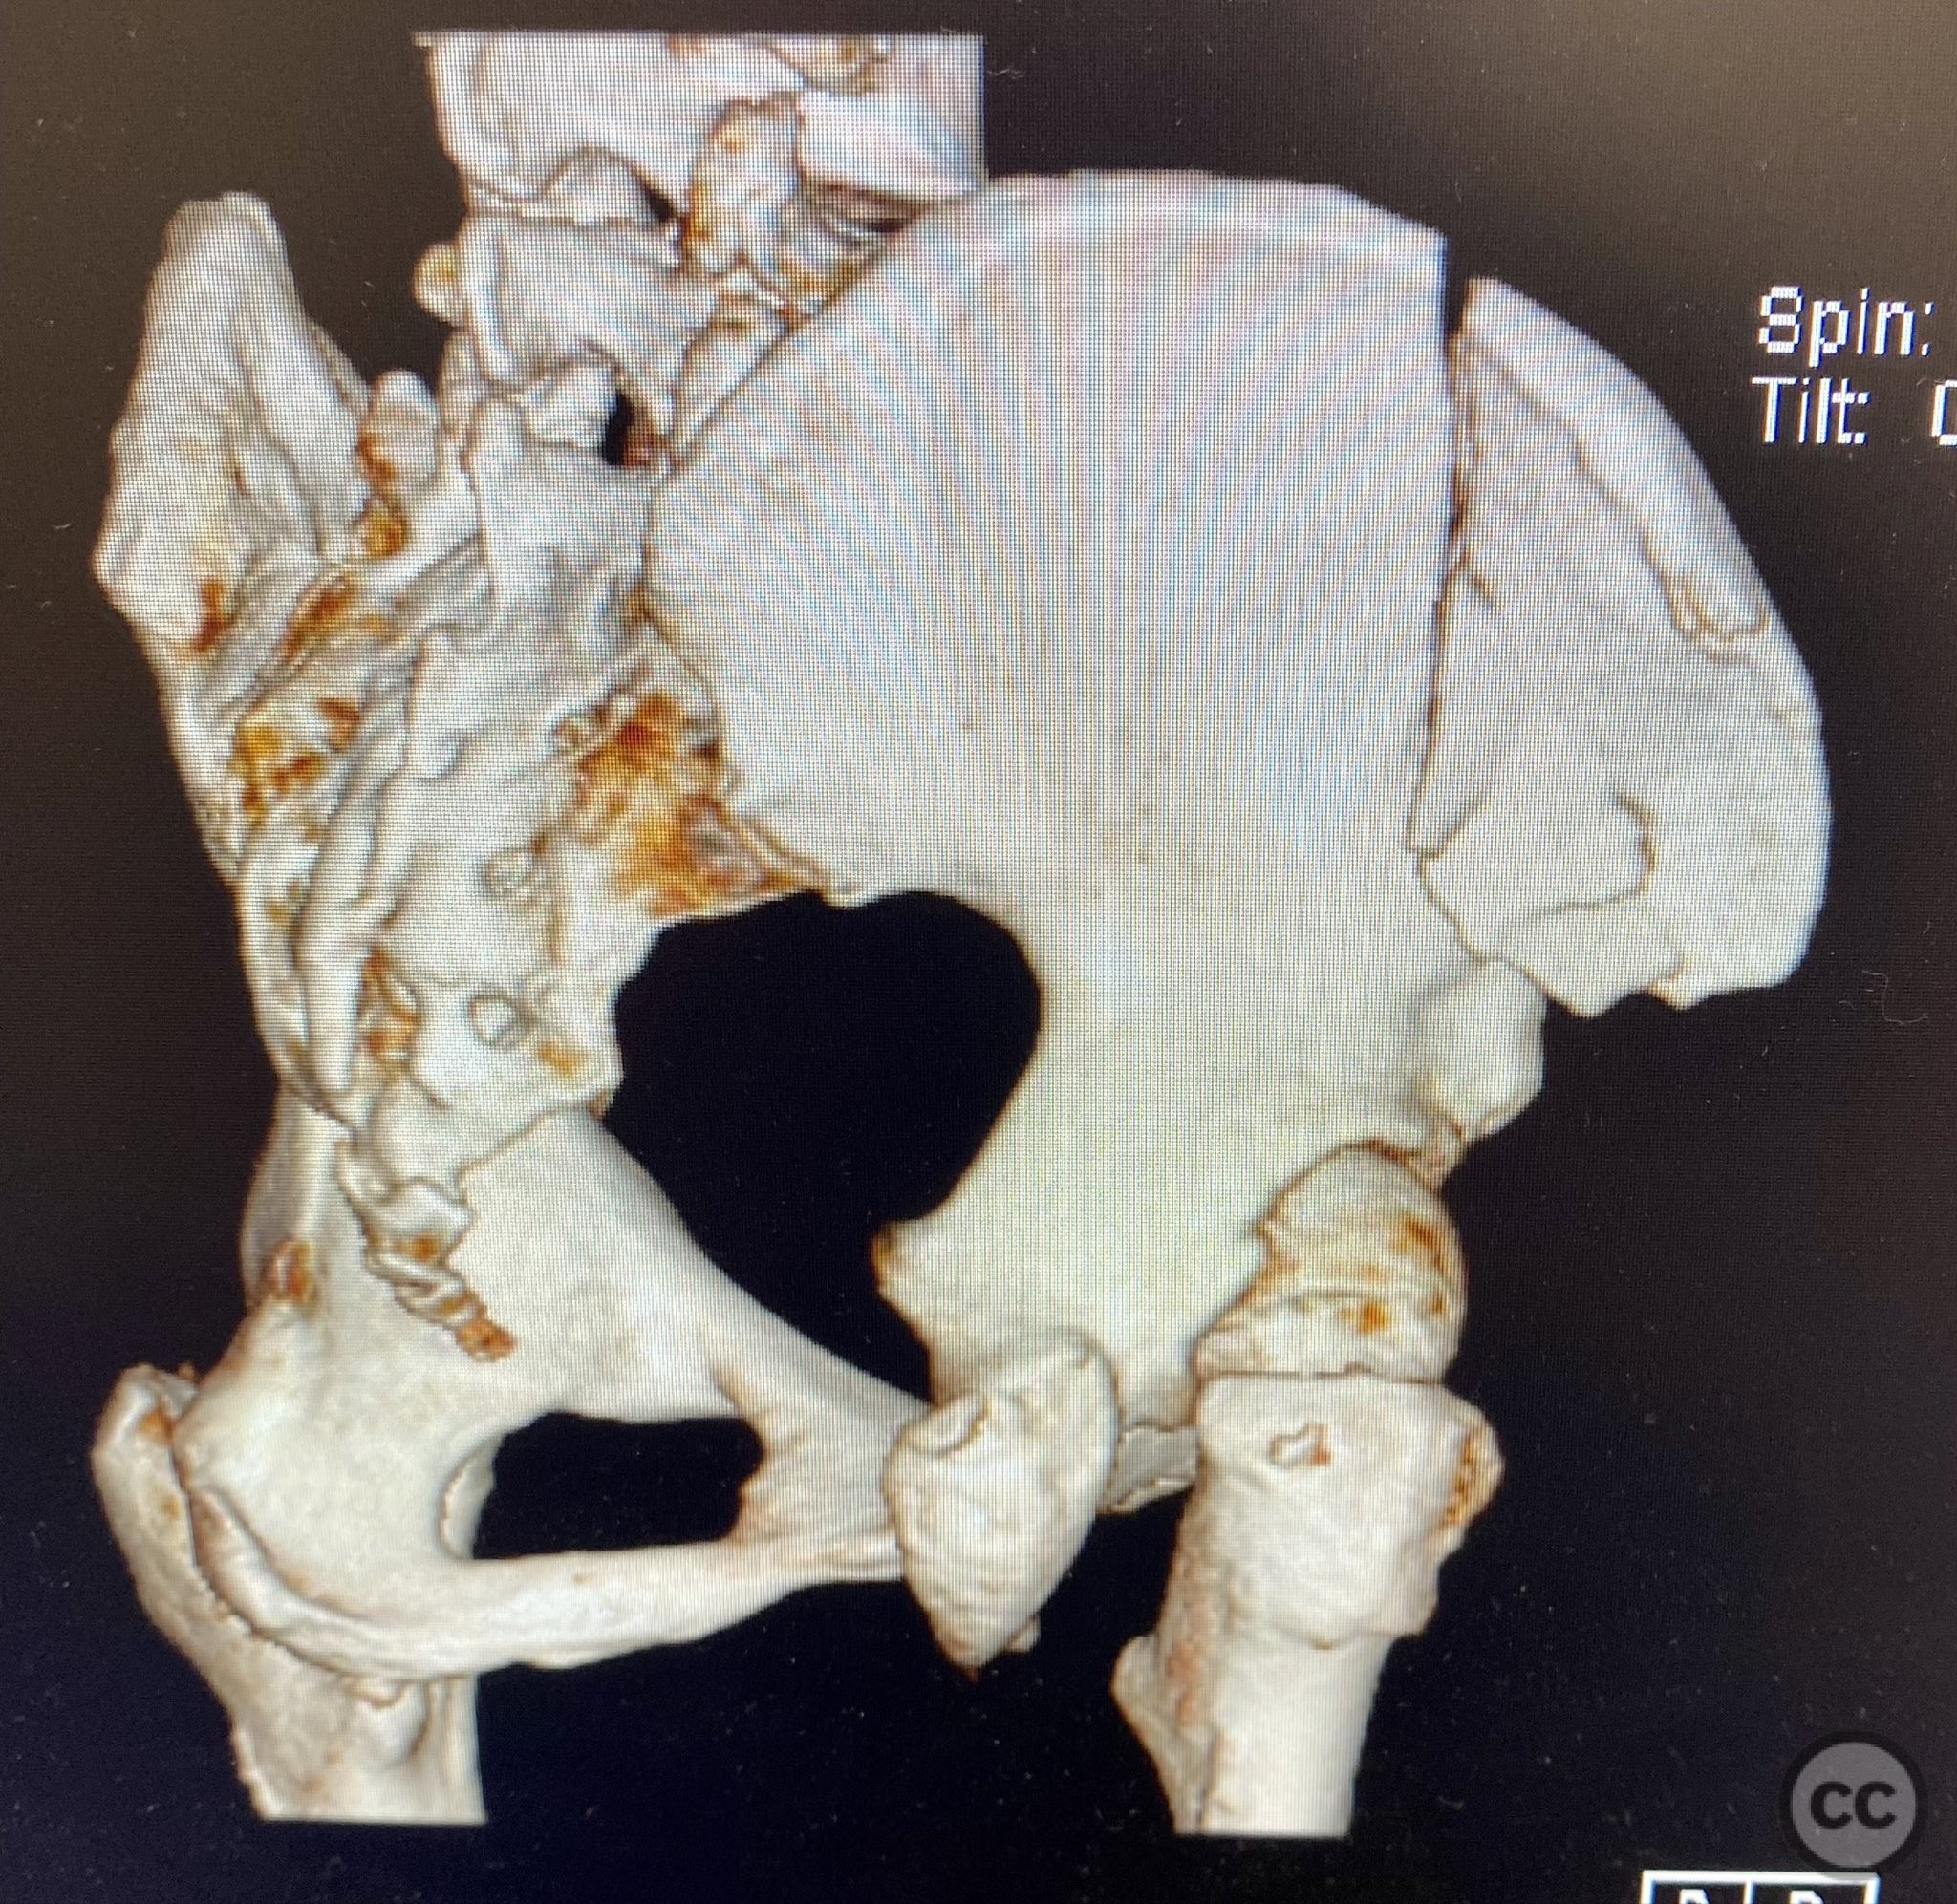

Clinical Details

Clinical and radiological findings:  A middle-aged patient sustained a closed, displaced, and comminuted fracture of the right os ilium following a fall from height. Initial AP pelvic radiograph and 3D surface rendered imaging demonstrated significant comminution, displacement, and poor bone quality. The patient was unable to mobilize due to pain. No associated neurovascular deficit or additional pelvic ring injury was reported. AO/OTA classification: 61B2.2 (partial articular, comminuted iliac wing fracture).